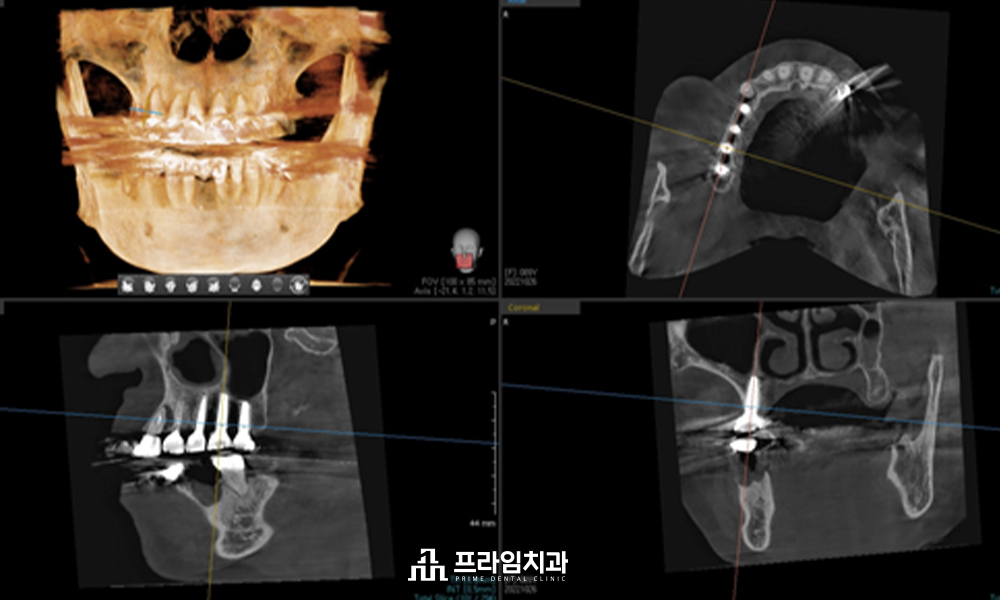

저희 치과에서는 임플란트

식립 전 3D CT와 구강 스캐너를

활용하여 육안으로 판단하기

힘든 구강 해부학적 구조물과

혈관 및 신경의 위치까지 면밀히

파악하여 1:1 맞춤 치료 계획을

수립하고 있습니다.